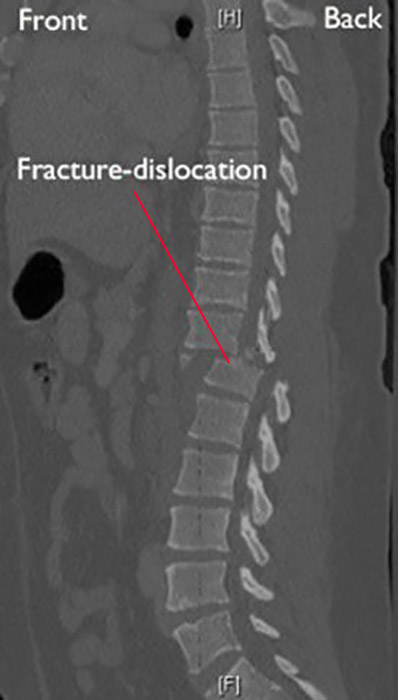

Vertebral facture-dislocation. Fracture-dislocation of the vertebra involves bone and/or soft tissue in which a vertebra moves off an adjacent (nearby) vertebra (displacement).

These injuries:

• Are unstable

• Frequently cause serious spinal cord compression

• Require surgery

Side view of a fracture-dislocation of a thoracic vertebra.

CT scan of fracture-dislocation in thoracic spine

A CT scan taken from the side of a fracture-dislocation in the

thoracic spine.

Surgical treatment. Fracture-dislocations of the thoracic and lumbar spine are caused by very high-energy trauma. They can be extremely unstable injuries that often result in serious spinal cord or nerve damage. These injuries require surgery to stabilize the spine. The ideal timing of surgery can often be complicated. Surgery is sometimes delayed because of other serious, life-threatening injuries.